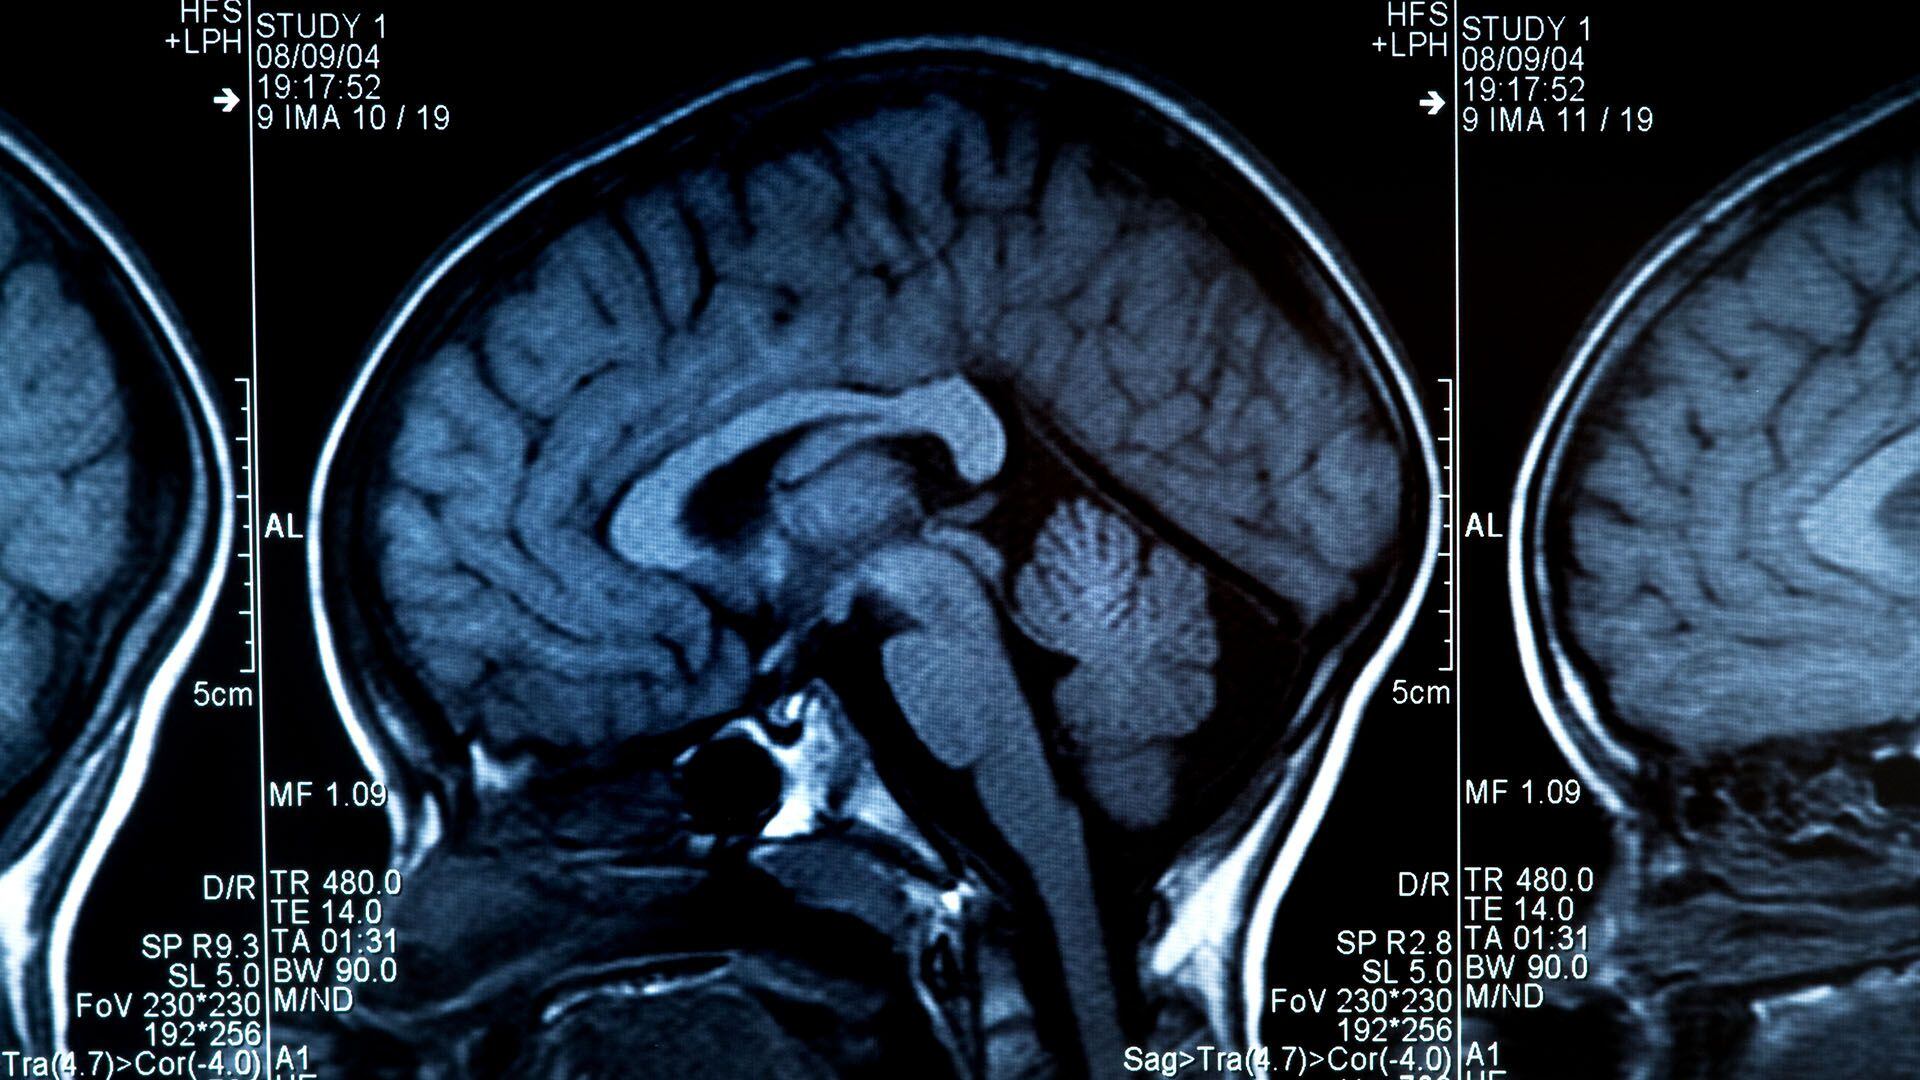

El envejecimiento cerebral afecta a los oligodendrocitos y a la integridad estructural de las vainas de mielina, esta última asociada a neuroinflamación. El principal factor de riesgo para la enfermedad de Alzheimer es la edad, aunque no está claro por qué. Se sabe que la capa aislante alrededor de las células nerviosas del cerebro, llamada mielina, se degenera con la edad.

“Aún no se han dilucidado los mecanismos subyacentes que explican la correlación entre la edad y la enfermedad de Alzheimer”, explicó Klaus-Armin Nave, director del MPI de Ciencias Multidisciplinarias. Con su equipo del Departamento de Neurogenética, investiga la función de la mielina, la capa aislante rica en lípidos de las fibras de las células nerviosas del cerebro. La mielina asegura la comunicación rápida entre las células nerviosas y apoya su metabolismo.

“Su presencia intacta es fundamental para la función cerebral normal. Hemos demostrado que los cambios en ella relacionados con la edad promueven cambios patológicos en la enfermedad de Alzheimer”, sostuvo Nave. En este nuevo estudio, los científicos exploraron el posible papel de la degradación de la mielina relacionada con la edad en el desarrollo de la enfermedad de Alzheimer. Su trabajo se centró en una característica típica de la enfermedad.

“La dolencia se caracteriza por el depósito de ciertas proteínas en el cerebro, los llamados péptidos beta amiloides —afirmó Constanze Depp, una de las dos primeras autoras del estudio—. Estos se agrupan para formar placas amiloides. En los pacientes de Alzheimer, éstas se forman muchos años e incluso décadas antes de que aparezcan los primeros síntomas”. En el curso de la enfermedad, las células nerviosas finalmente mueren de forma irreversible y la transmisión de información en el cerebro se ve perturbada.

Usando imágenes y métodos bioquímicos, los científicos examinaron y compararon diferentes modelos de ratones con Alzheimer en los que las placas de amiloide se comportan de manera similar a las de los pacientes humanos. Sin embargo, por primera vez, estudiaron ratones con Alzheimer que además tenían defectos de mielina, que también ocurren en el cerebro de las personas con una edad avanzada.

Ting Sun, segundo primer autor del estudio, describió los resultados: “Vimos que la degradación de la mielina acelera la deposición de placas amiloides en el cerebro de los ratones. Su presencia defectuosa estresa las fibras nerviosas, lo que hace que se hinchen y produzcan más péptidos”.

Sin embargo, cuando se enfrenta tanto a la mielina defectuosa como a las placas, elimina principalmente los restos de mielina mientras las placas continúan acumulándose. Los investigadores sospechan que la microglía está “distraída” o “abrumada” por el daño de la mielina y, por lo tanto, no puede responder adecuadamente a las placas. Los resultados del estudio mostraron, por primera vez, que la mielina defectuosa en el cerebro que envejece aumenta el riesgo de depósito del péptido beta amiloide.